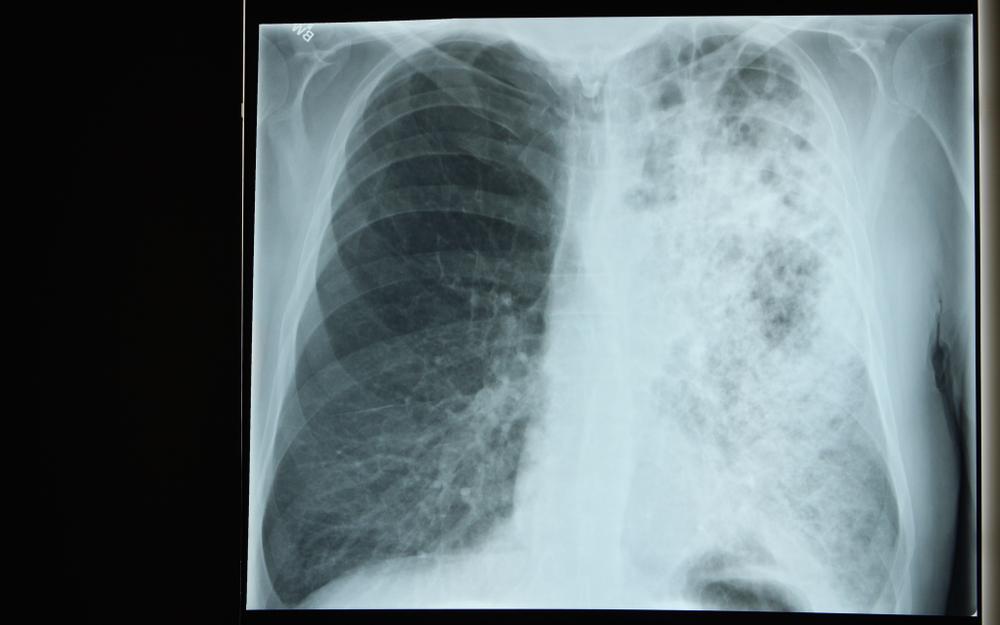

Penyakit Legionnaires adalah sejenis radang paru-paru (pneumonia) parah yang terjadi ketika bakteri legionella menginfeksi paru-paru.

Tak hanya pernapasan, penyakit ini juga dapat memengaruhi otak dan sistem pencernaan.

Legionnaires merupakan penyakit radang paru-paru parah yang memerlukan penanganan medis. Apabila dibiarkan begitu saja, Anda berpotensi mengalami sejumlah komplikasi berikut.

1. Gangguan sistem pernapasan

Ketika paru-paru tidak mendapat cukup asupan oksigen dari darah, sistem pernapasan akan terganggu. Untuk membantu bernapas, beberapa pengidapnya mungkin memerlukan ventilator.